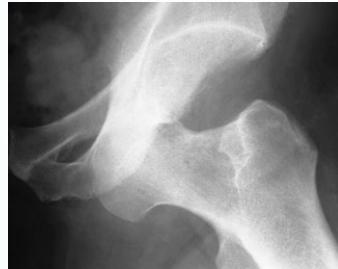

Anterior Hip Dislocation

- Rare

- The leg lies externally rotated, abducted & slightly flexed

- Palpable head in the groin